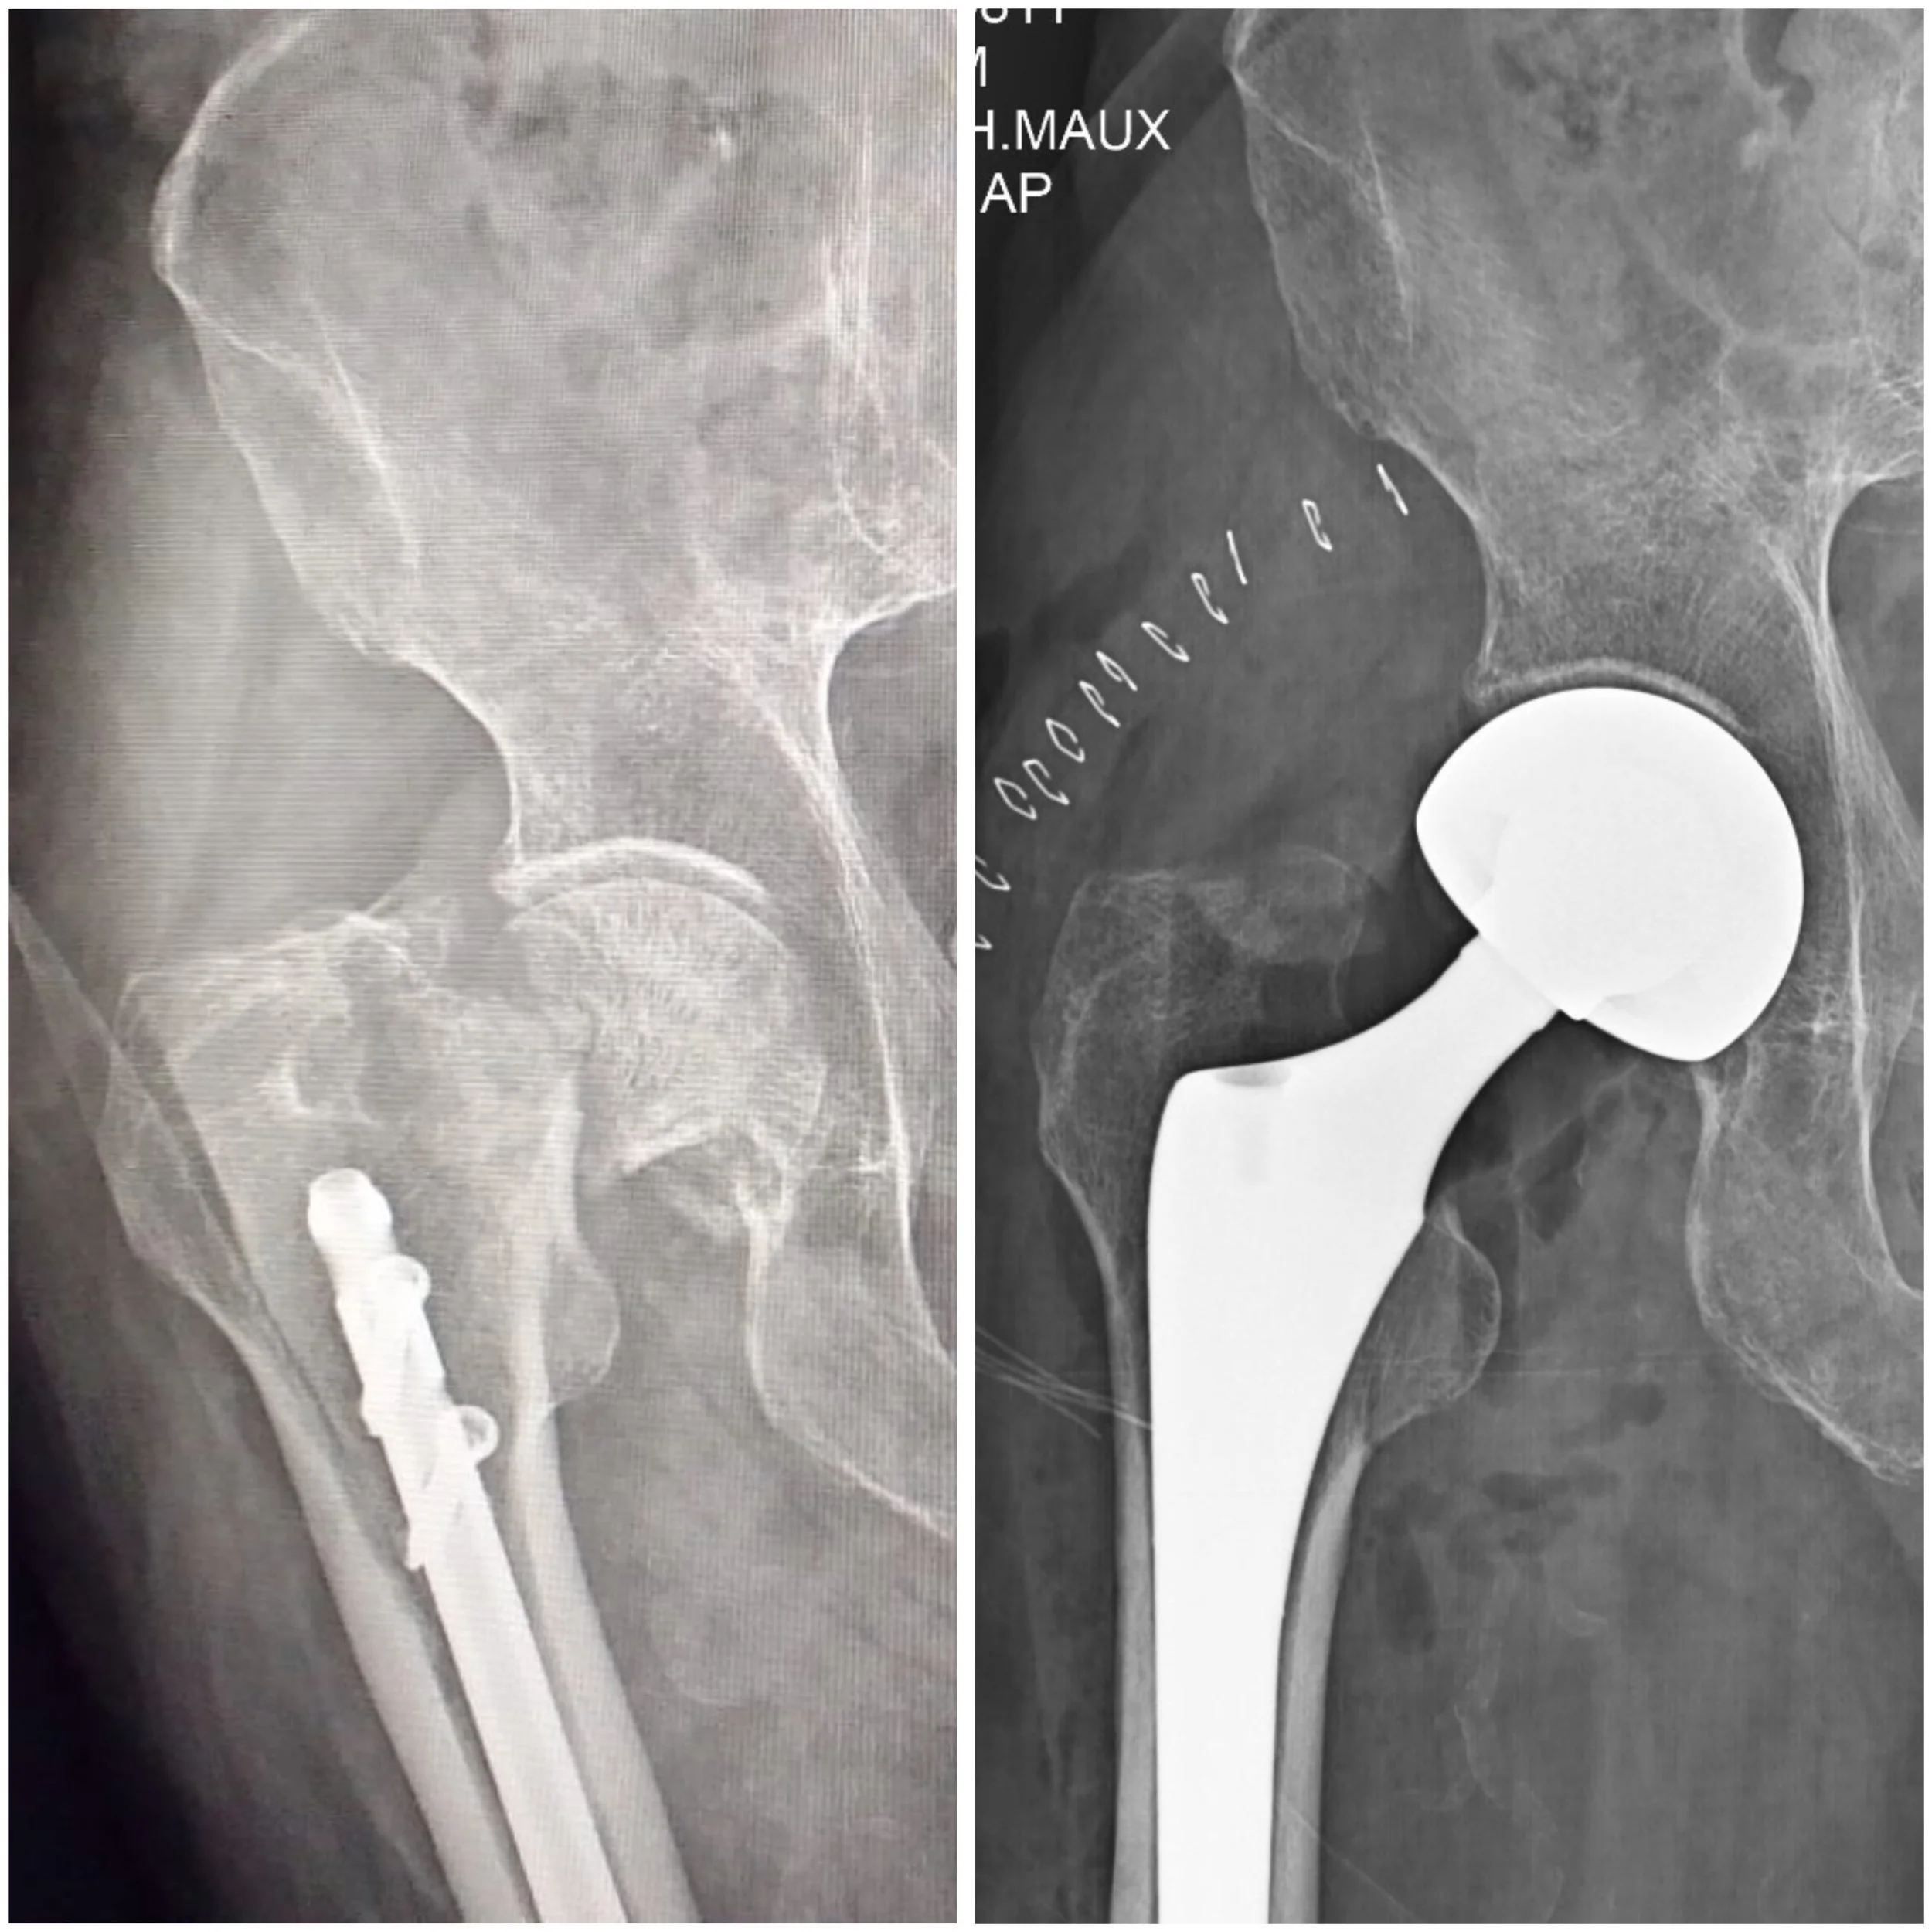

Imágenes de radiografías de pelvis y cadera, una en escala de gris claro y otra en escala de gris oscuro con letras y números médicos.

Fractura de cadera

La fractura de cadera es una lesión importante que con frecuencia ocasiona dolor intenso, incapacidad para caminar y limitación funcional importante. En muchos casos ocurre después de una caída, especialmente en pacientes mayores, aunque también puede presentarse en otros contextos dependiendo del mecanismo de lesión.

El tratamiento se define según el tipo de fractura, la edad del paciente, su estado funcional previo y sus condiciones generales de salud. En algunos casos se requiere manejo quirúrgico para estabilizar la fractura o reemplazar la articulación. Una valoración oportuna es fundamental para establecer el tratamiento más adecuado y buscar una recuperación funcional temprana.